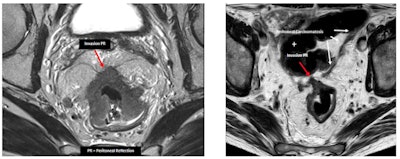

The treatment of a patient with rectal cancer mainly depends on the TNM (tumor, node, metastasis) stage and whether the mesorectal fascia (MRF) is involved. A T3b stage rectal tumor with MRF involvement (left, red arrows) compared to a T3c tumor with free MRF (right, red arrow). MRF involvement clearly worsens the prognosis of the tumor with a lower category of T staging. All images courtesy of Dr. María Canedo Antelo et al and presented at ECR 2023.

The treatment of a patient with rectal cancer mainly depends on the TNM (tumor, node, metastasis) stage and whether the mesorectal fascia (MRF) is involved. A T3b stage rectal tumor with MRF involvement (left, red arrows) compared to a T3c tumor with free MRF (right, red arrow). MRF involvement clearly worsens the prognosis of the tumor with a lower category of T staging. All images courtesy of Dr. María Canedo Antelo et al and presented at ECR 2023."MRF status is one of the most important risk factors for recurrence," they wrote. "A positive MRI-assessed margin between the tumor and MRF is defined as tumor lying within 1 mm of the MRF."

The MRF is a hypointense line on T2-weighted MRI, but it is a multilayered envelope that presents with gaps, and at some points it may not be visible on imaging. It is juxtaposed to the parietal fascias, which have different names according to location, they continued. Anteriorly, from the pelvic floor to the peritoneal reflection is the Denonvilliers' fascia; posteriorly, covering the sacrum, is the presacral fascia, which continues anteriorly as the pelvic parietal fascia.